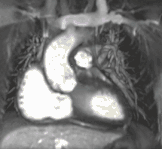

نقص مادرزادی قلب شایعترین نوع عمده نقص تولد است. تشخیص دقیق برای تدوین برنامههای درمانی مناسب ضروری است. CMR میتواند بدون استفاده از اشعه ایکس یا ورود به بدن اطلاعات کاملی در مورد ماهیت نقایص مادرزادی قلب به روشی ایمن ارائه دهد. این روش، به ندرت بعنوان اولین یا تنها آزمایش تشخیص بیماری مادرزادی قلب استفاده میشود.

در عوض، این روش معمولاً با سایر روشهای تشخیصی به صورت هماهنگ استفاده میشود. بهطور کلی، دلایل بالینی برای معاینه CMR در یک یا چند دسته زیر قرار میگیرد: (۱) هنگامی که اکوکاردیوگرافی (سونوگرافی قلبی) نمیتواند اطلاعات تشخیصی کافی را ارائه دهد، (۲) به عنوان جایگزینی برای روش تشخیص کاتتریزاسیون قلبی که شامل خطرات از جمله قرار گرفتن در معرض اشعه x است، (۳) برای به دست آوردن اطلاعات تشخیصی که CMR مزایای منحصر به فردی مانند اندازهگیری جریان خون یا شناسایی تودههای قلبی را ارائه میدهد، و (۴) هنگامی که ارزیابی بالینی و سایر آزمایشهای تشخیصی مغایر هستند. نمونههایی از شرایطی که CMR اغلب در آن استفاده میشود شامل تترولوژی فالوت ، انتقال شریانهای بزرگ، انسداد آئورت، بیماری قلبی منفرد بطن، ناهنجاری رگهای ریوی، نقص دیوارهٔ بین دهلیزی، بیماریهای بافت همبند مانند سندرم مارفان، حلقههای عروقی، منشأ غیرطبیعی شریانهای کرونر و تومورهای قلبی است.

نقص دیواره بین دهلیزی با اتساع بطن راست توسط CMR

تخلیه وریدی ریوی غیرعادی جزئی توسط CMR